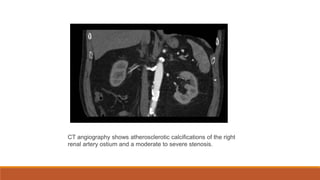

CT angiography shows atherosclerotic calcifications of the right

renal artery ostium and a moderate to severe stenosis.

CT angiography showsatherosclerotic calcifications of the right renal artery ostium and a moderate to severe stenosis.